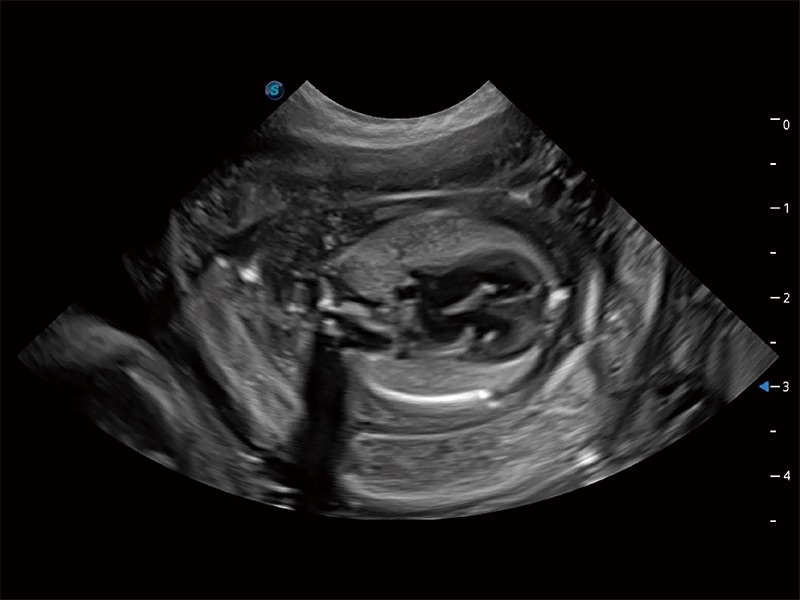

ProPet 80 配备了丰富的心脏探头群、先进的成像技术和专业的心脏测量工具,可帮助动物医生为不同体型和生理结构的动物提供心脏和心肌功能的全面评估。

实时用颜色表示心肌组织运动,观察和定量组织的运动情況,对快速检测与评估心肌的灌注和活性、电传导及心肌收缩和舒张功能等均能提供重要的诊断信息。

通过心肌识别技术与二维斑点追踪技术相结合,对心脏的超声图像进行量化分析。计算心肌17个节段的应变、应变率、速度、位移等,并通过牛眼图的形式进行呈现。